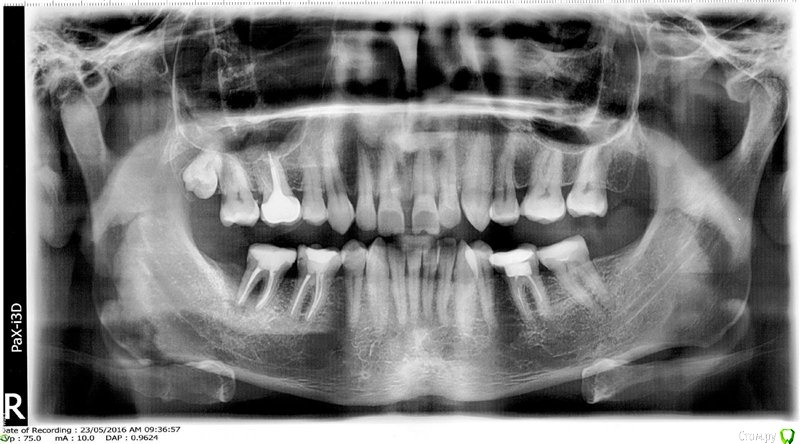

Slava76 Опубликовано 5 декабря, 2020 Поделиться Опубликовано 5 декабря, 2020 Всем доброго дня!Три дня назад с утра появилась боль в нижней челюсти слева. Сначала было не понятно, что болит зуб или мышцы. Но боль шла из под двух крайних коренных зубов. На крайнем зубе коронка, которую установил пару лет назад, зуб живой. У другого зуба пломба, которую установили около 10 лет назад, нервы удалены. Постучал чайной ложкой по этим зубам, боль не усилилась. От холодного, горячего боль так же не усиливается. К вечеру небольшая боль ощущалась только при сжимании зубов. На следующий день с утра все повторилось, с утра болело сильней, к вечеру слабей. Сходил на прием к стоматологу. Сделали снимок, см. вложение. Врач сказал, что у крайнего зуба коронка стоит хорошо, но под коронкой в зубной ткани он видит трещину. Для того, чтобы понять действительно ли она есть и какого размера посоветовал сделать КТ. У зуба под пломбой один канал не долечен, в другом сломали медицинской инструмент. Каких то воспалений он не увидел. Он считает, что боль может вызывать как один, так и другой зуб. Если есть трещина под коронкой, то вылечить зуб нельзя. Только удаление. Если "виноват" зуб под пломбой, то можно перелечить каналы и поставить коронку. В итоге сказал немного подождать, если боль не пройдет, то делать КТ и уже решать. Боль не проходит. Она не сильная, не стреляющая, терпеть ее легко. По ощущениям кажется, что боль идет от зуба под коронкой, но не уверен. Что посоветуете делать дальше? Врач, у которого был, достаточно молод. Хочется услышать еще одно мнение.Заранее благодарю за советы! Ссылка на комментарий

Slava76 Опубликовано 5 декабря, 2020 Автор Поделиться Опубликовано 5 декабря, 2020 (изменено) Почему-то не подгрузился снимок. ДобавляюЕще добавлю снимок всех зубов, который делали в 2016 г. Изменено 5 декабря, 2020 пользователем Slava76 Ссылка на комментарий

DmitrySH Опубликовано 5 декабря, 2020 Поделиться Опубликовано 5 декабря, 2020 Под коронкой скорее всего не трещина, а так видно строение зуба. У зуба где сломан инструмент - есть воспаление. Начните с его лечения. Ищите эндодонтиста работающего с микроскопом 1 Ссылка на комментарий

wladdX Опубликовано 7 декабря, 2020 Поделиться Опубликовано 7 декабря, 2020 (изменено) Трещины в зубе 37 не увидел Изменено 7 декабря, 2020 пользователем wladdX Ссылка на комментарий